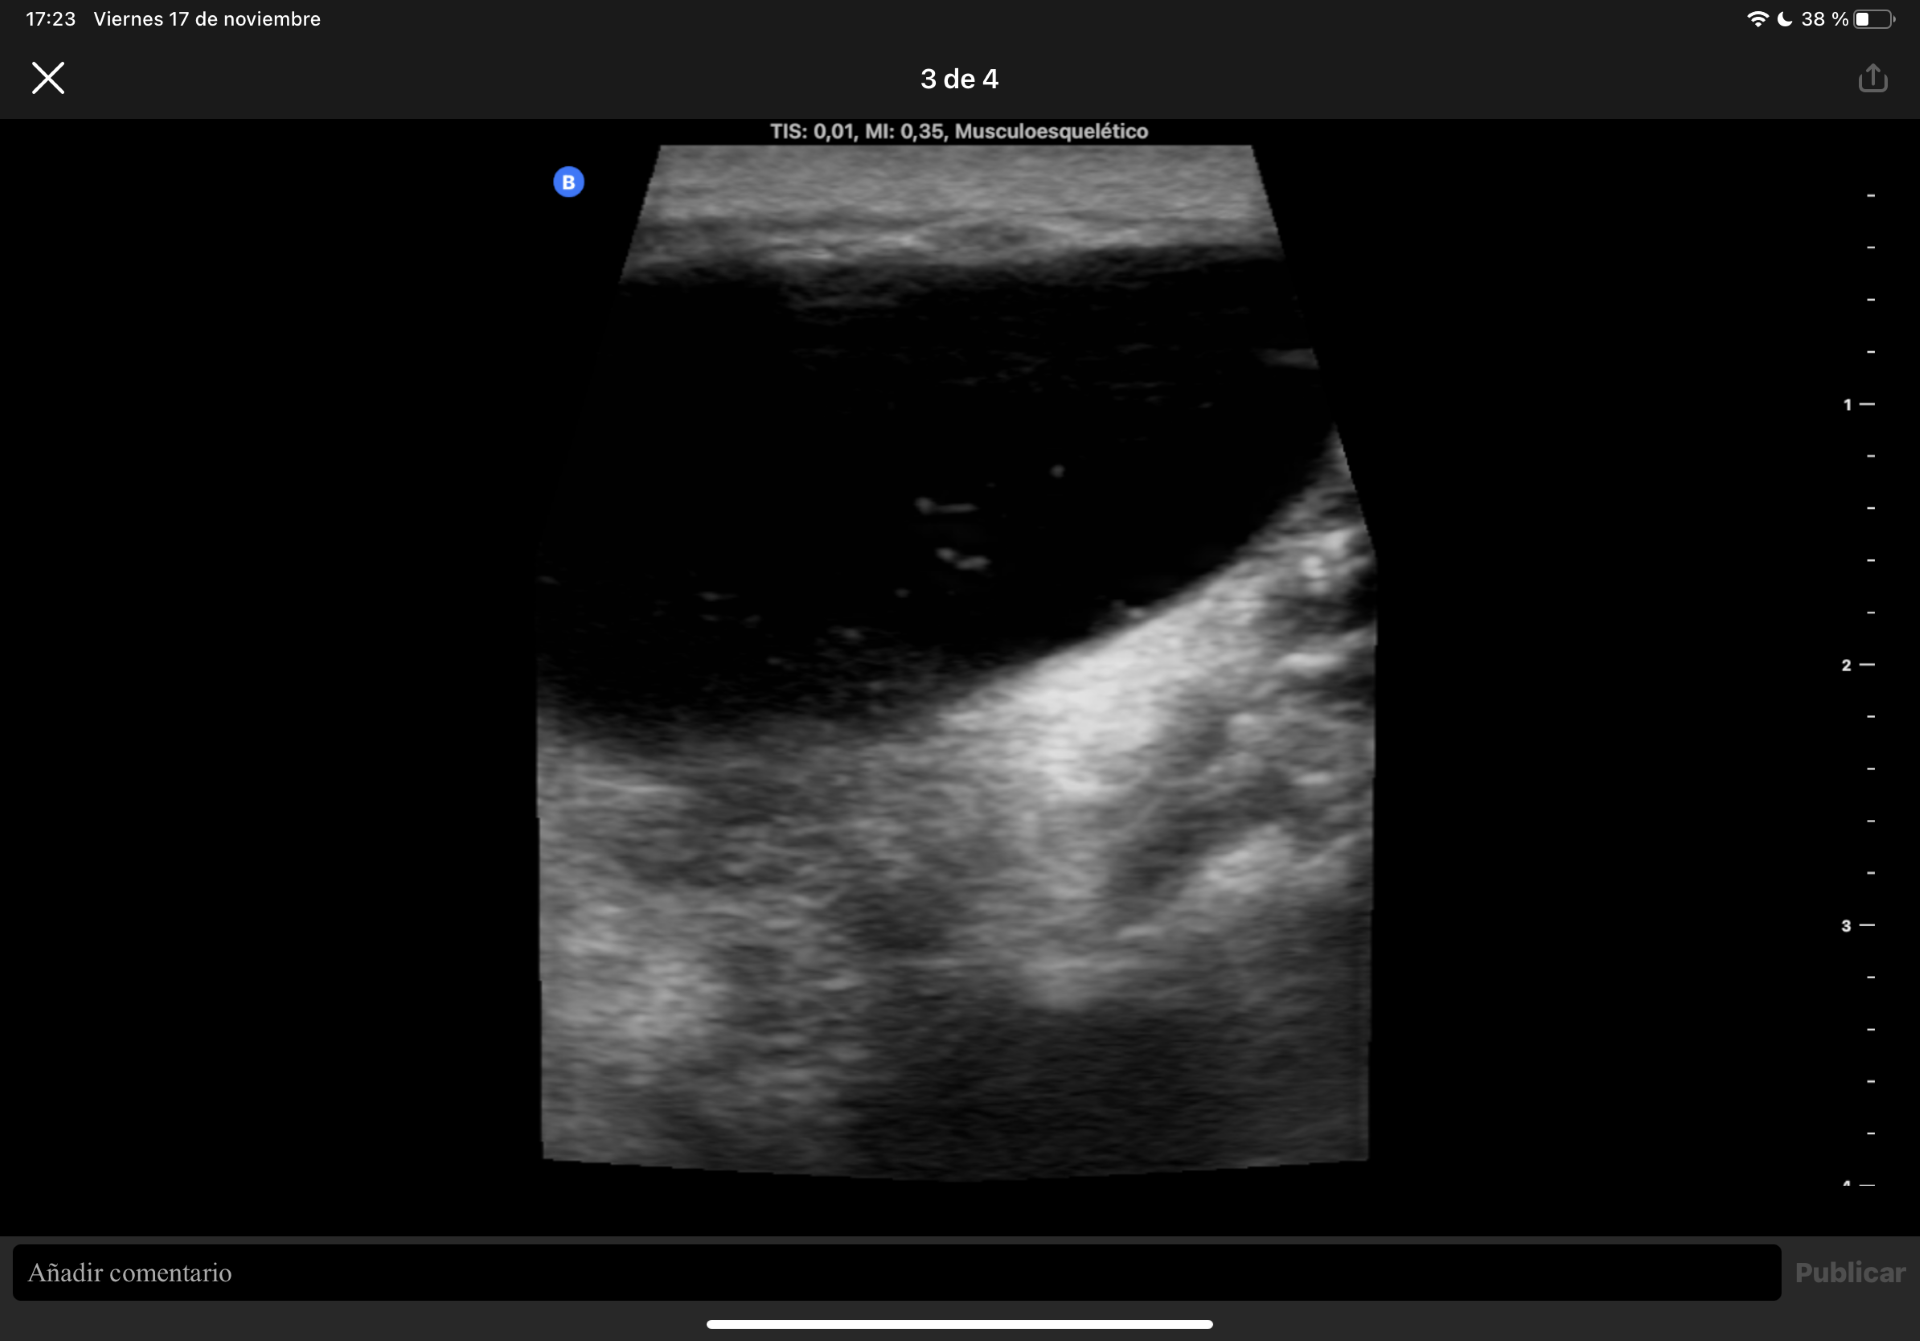

Ante la sospecha de quiste sinovial se realiza Ecografía músculo esquelética en consulta.

Difícil acceso por las forma de la masa. Se observa en plano dérmico lesión sin pared de 1,85 cm en su mayor altura, aneicoica con flóculos en su interior. No parece depender de la articulación del hombro ni la acromionclavicular, no se aportan más medidas por salirse de la ventana del ecógrafo.

Ecografía de Radiología: La masa que se palpa en el hombro izquierdo se corresponde con una masa quística que nace desde la articulación acromionclavicular en relación con rotura del manguito de los rotadores identificándose compromiso del supra e infraespinoso.